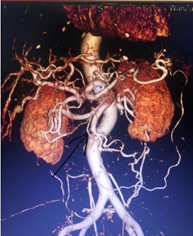

经会诊研判,考虑患者可能患肠系膜上动脉栓塞,因此将患者转入普外科接受住院治疗,并为患者进行肠系膜动脉CTA检查,检查结果显示:该患者腹腔动脉硬化、肠系膜上动脉中段及肠系膜下有动脉斑块并存在管腔高度狭窄的情况,患者情况十分危急,需尽快开展手术,稳定生命体征。

术中取栓前后肠系膜上动脉造影对比